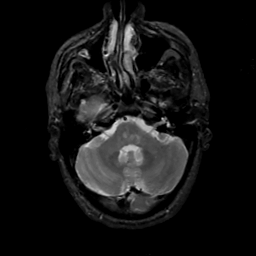

MR Study #12, May 12, 1991 -- Slice #11

[Home][Help][Clinical][Tour 1][Tour 2] Slice 11